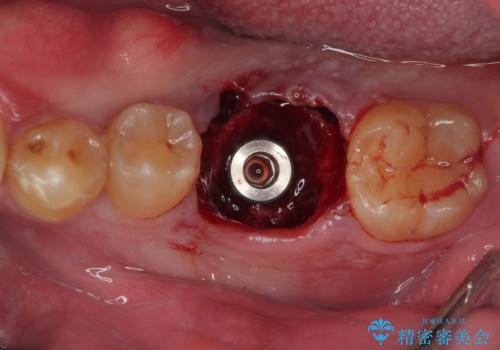

インプラント埋入時に植立具合の安定性を測定したところ、十分な数値が得られたため、速やかに仮歯を装着して咬合回復をさせることができました。

抜歯を含めた外科処置を1回に抑えることができ、あっという間に治療を終えることができました。